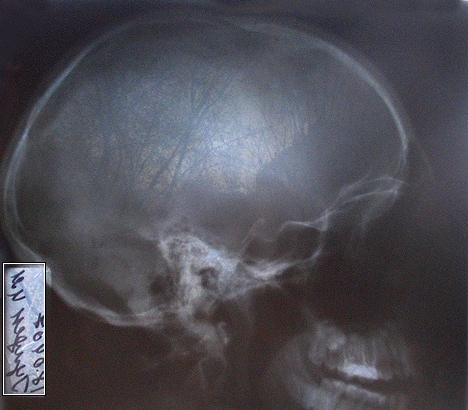

— За направленням Бахмацької районної лікарні. Стан тяжкий: відкрите вогнепальне поранення голови. При тямі її оглянули лор, окуліст. Провели комп'ютерну томографію. Мозок постраждав, але не дуже сильно. І, враховуючи локалізацію куль, які, на щастя, не пошкодили життєво важливі органи, хвору вирішено було не оперувати, а лікувати медикаментозно.

— Тобто жінка продовжуватиме жити з двома кулями в голові?

Переді мною знімки черепа Віри Василівни. У фас і в профіль. На них просвічуються два доволі великих предмети, схожі на дві гирки. Важко повірити, що, маючи це в голові, людина може говорити, думати...

— Це можливо. Адже багато людей носить у собі осколки куль з війни, — пояснює Геннадій Іванович.

— Кулі засіли так, що операційний ризик набагато перевищував результати, які б ми могли отримати, якби операцію провели. Куля застрягла в кістці, тому хвора залишилася жива. Але якби якась йота в бік...

Друга куля зайшла в ділянці щоки зліва від носа і застрягла перед першим шийним хребцем. Ще трохи, і шию б відірвало. Третя пройшла навиліт через підборіддя.

— Дивні кулі. Ви такі зустрічали? Чому така форма?

—Самі кулі циліндричні, але на травматику щось не схожі.

Рентгенівській знімок Віри Євтух